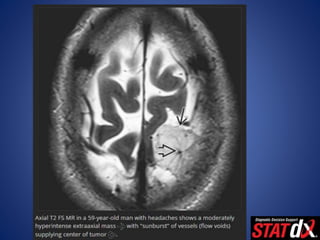

• T2WI

– Variable ("sunburst" pattern may be evident)

– 8-23% of intratumoral cysts (common; can be almost microcystic),

hemorrhage (rare)

– Best sequence for

• Visualizing CSF/vascular cleft between tumor, brain (80%)

• Identifying vascular flow voids (80%)

• Predicting "hard" meningioma at surgery (hypointense)

– "Sunburst" or radial appearance

• Dural vessels supply lesion core

• Pial vessels may be parasitized, supply periphery

– Prolonged vascular "stain"

– Venous phase vital to evaluate sinus involvement